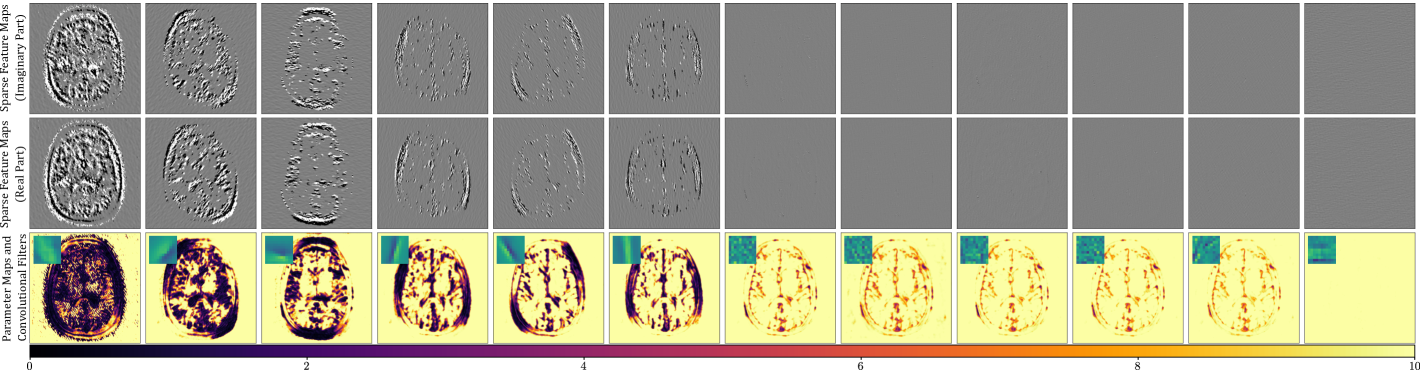

In Figure 2 we see an example of 12 sparse feature maps estimated by FISTA as well as the corresponding learned regularization parameter maps and their associated filters. From the parameter maps, we see that the network seems to be able to distinguish between more and less useful filters for the sparse approximation. Note that higher values in the -maps result in a higher threshold in the proximal operator of and thus to a lower contribution in the sparse representation.